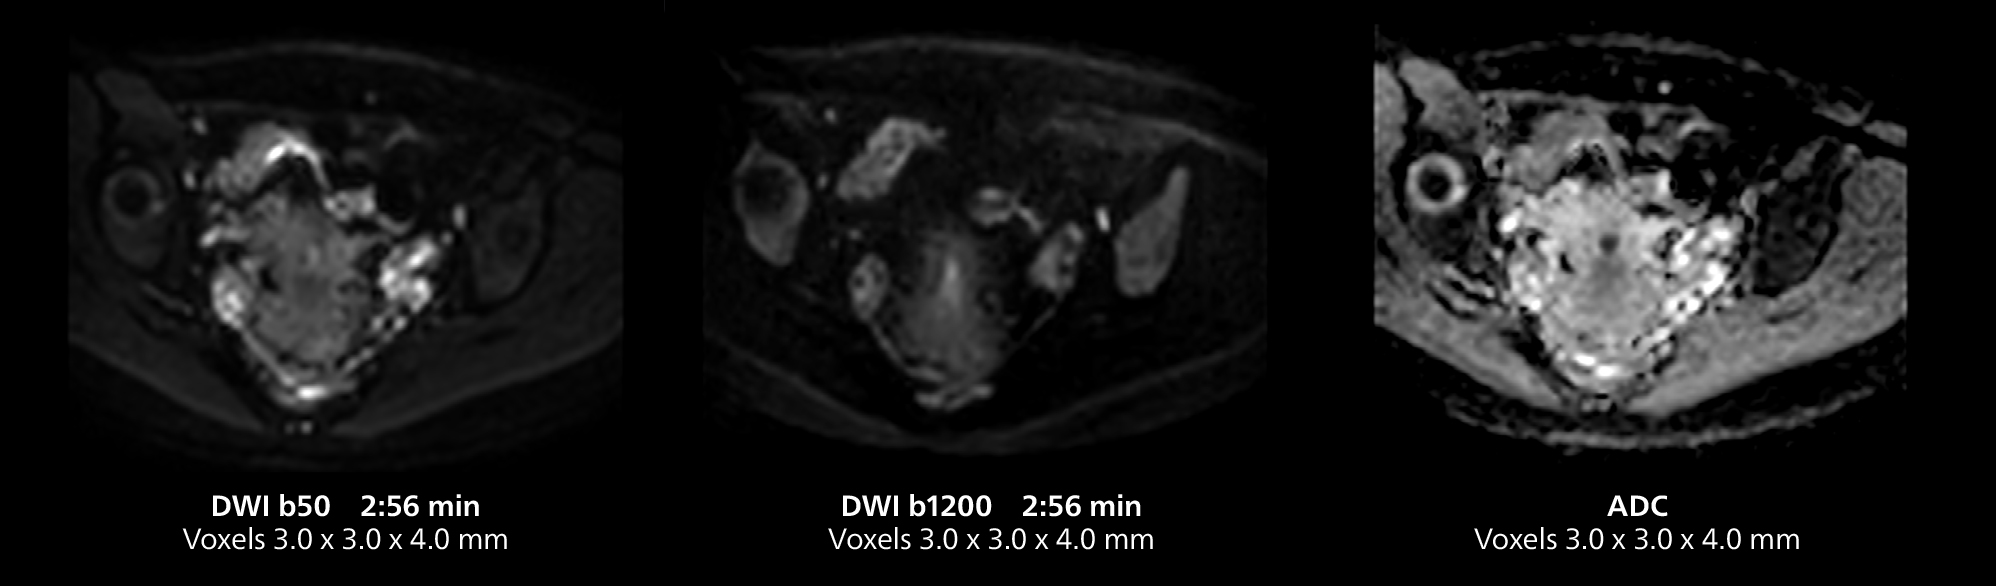

This MRI case illustrates good resolution and imaging quality obtained within reasonable scan times using the MR 5300 1.5T system with the anterior torso cardiac coil that allows use of a large field of view (FOV).